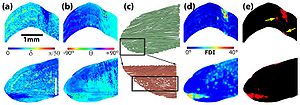

- 3.49 Optical Polarization Tractography Revealed Significant Fiber Disarray in Skeletal Muscles of a Mouse Model for Duchenne Muscular Dystrophy